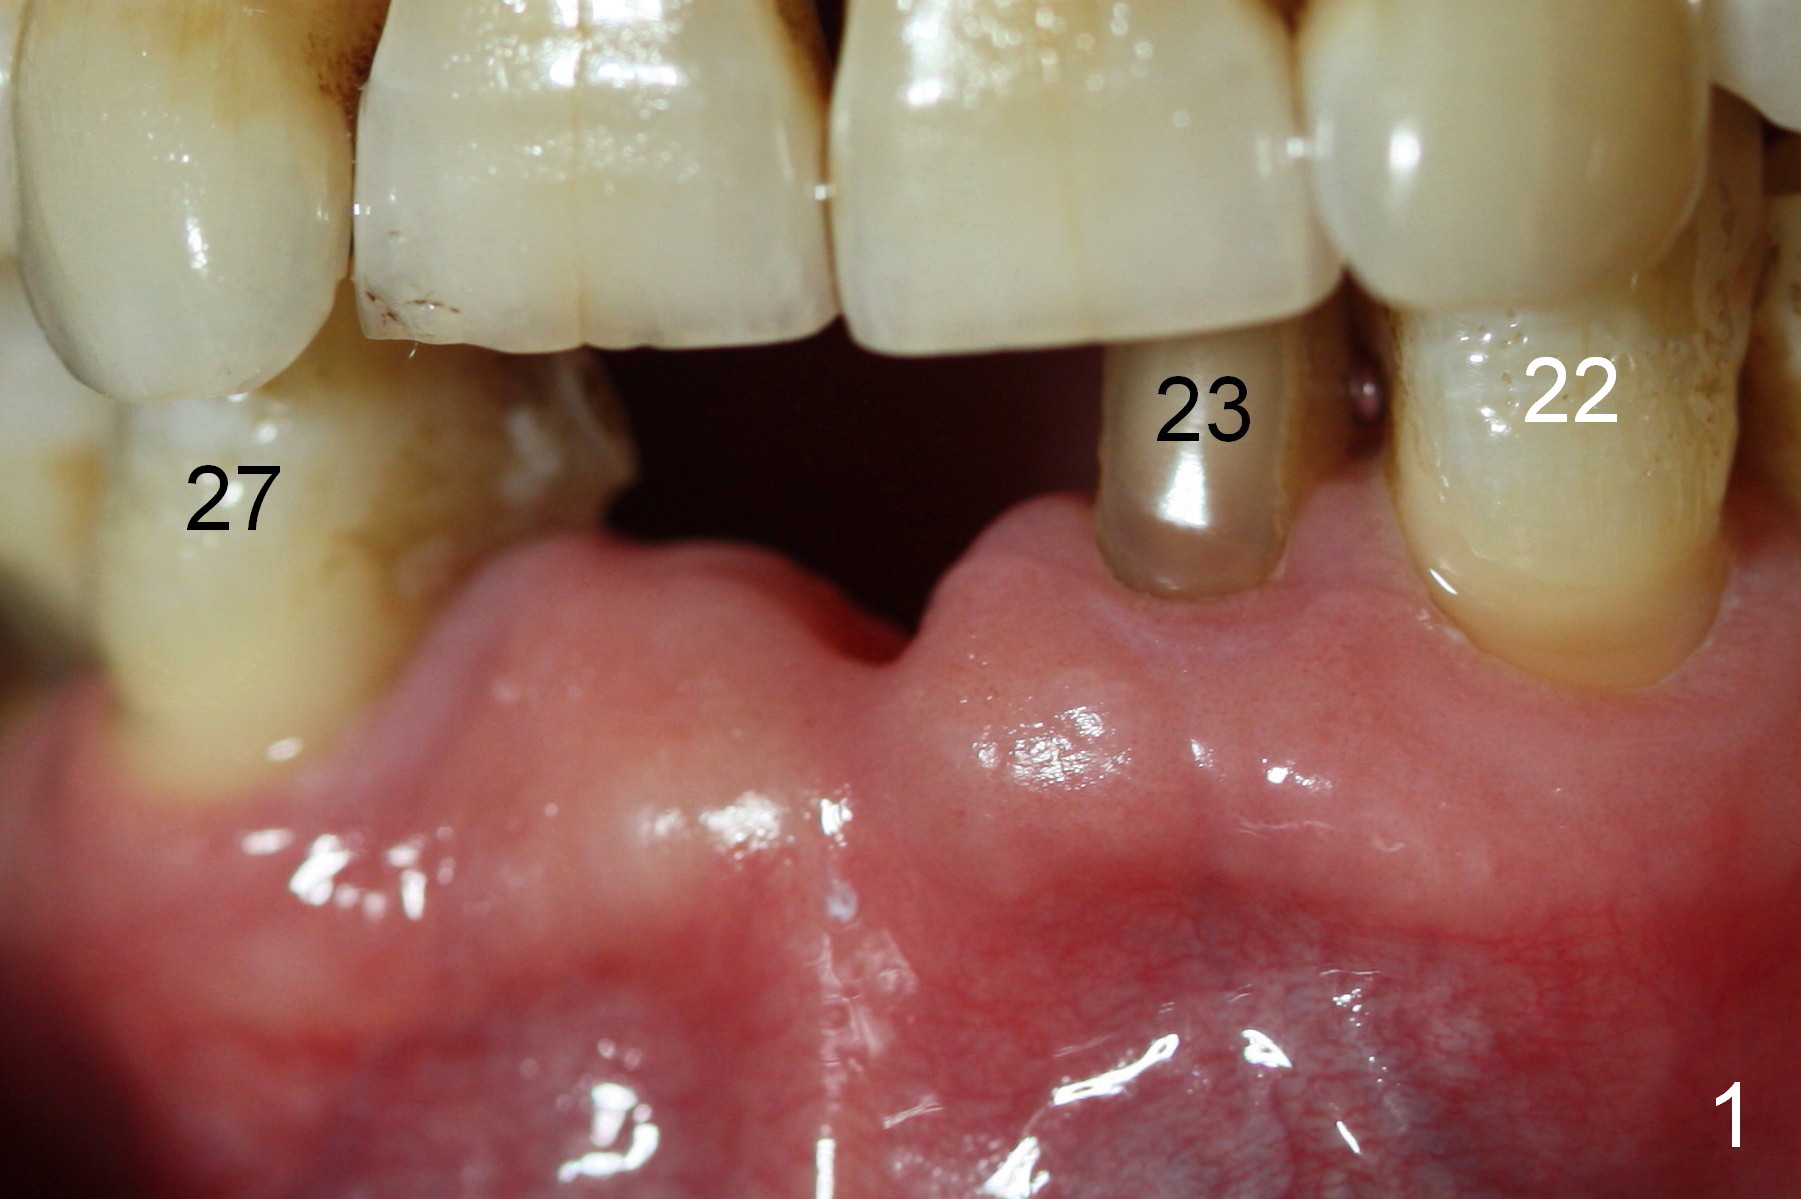

The teeth give the gingiva scallop shaped (Fig.1, 2). The scallop is less where the tooth is absent (Fig.2 *). The scallop must have been distinct when the tooth is just extracted with prominent papillae (Fig.2,3 ^).